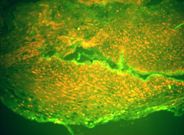

La histopatologia Nº 02-189, realizada en la Cátedra de Anatomía Patológica General y BMF de la Facultad de Odontología, informó que se trataba de epitelio malpighiano con francas hendiduras entre epitelio integro y el corion. El conjuntivo presentaba infiltrado inflamatorio moderado linfoplasmocitario con eosinófilos escasos e hiperplasia endotelial vascular (Foto 5)

Foto 5 Desprendimiento in toto del tejido conjuntivo y presencia de neovasos

El estudio histopatológico (Nº 03-129) realizado en la Cátedra de Anatomía Patológica General y BMF de la Facultad de Odontología, informó que se trataba de una ampolla subepitelial. El epitelio se mantenía en áreas adosado a la membrana basal. El conjuntivo presentaba un infiltrado inflamatorio linfocitario, con neutrófilos, plasmocitos, abundantes mastocitos y neovasos (Fotos 8 – 10).

Foto 8 Hendidura entre epitelio de cubierta y tejido conjuntivo. Ampolla subepitelial

Foto 9 Infiltrado de linfocitos, neutrófilos y plasmocitos

Foto 10 Presencia en conjuntivo de mastocitos y neovasos. Alteración de células basales

El estudio de los tejidos en el microscopio óptico demuestra, una separación nítida entre epitelio y conjuntivo, llamada ampolla o bulla subepitelial. Este epitelio mantiene la capa de células basales y por debajo de él, se observan desde suaves hendiduras a francas luces subepiteliales que se extienden a lo largo de la superficie.

El techo que conforma la parte superior de la ampolla está constituido por un epitelio atrófico y comprimido en todo su espesor. El contenido de estas ampollas es sero-fibrinógeno con eosinófilos y neutrófilos. El inicio de la enfermedad se caracteriza por una reacción inflamatoria rica en eosinófilos y linfocitos, pero con escasos plasmocitos, dispuestos en forma difusa hacia la profundidad del tejido conectivo papilar edematoso.

En general el infiltrado inflamatorio es de grado variable en el tejido conjuntivo, con abundantes células plasmáticas y a veces con presencia de eosinófilos y neutrófilos. Además existe dilatación de los vasos sanguíneos, acompañado por un moderado infiltrado inflamatorio que abarca de la superficie hasta la profundidad del corion.

La repetición de los brotes evolutivos en la misma zona, conduce a la atrofia de las papilas del corion y a la neoformación de los vasos capilares, con reacción fibrosa y acúmulos de densos infiltrados linfoplasmocitarios.